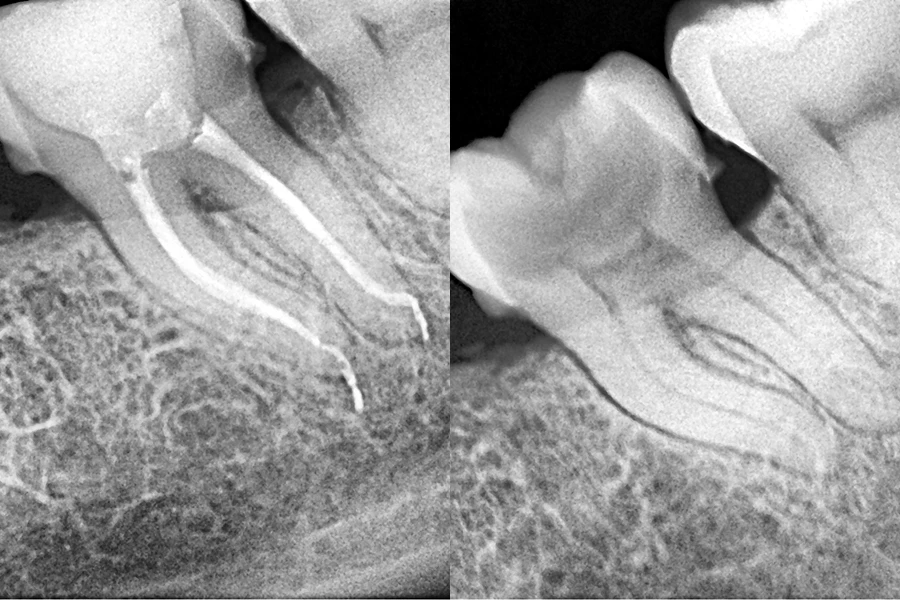

Endodoncia

Tratamiento preciso para salvar dientes dañados. Eliminamos infecciones y preservamos dientes afectados por caries profundas o traumatismos con endodoncia de alta precisión. Con el microscopio dental y la tomografía computarizada, diagnosticamos y tratamos la pulpa dental con exactitud, evitando extracciones innecesarias y mejorando tu salud bucal.